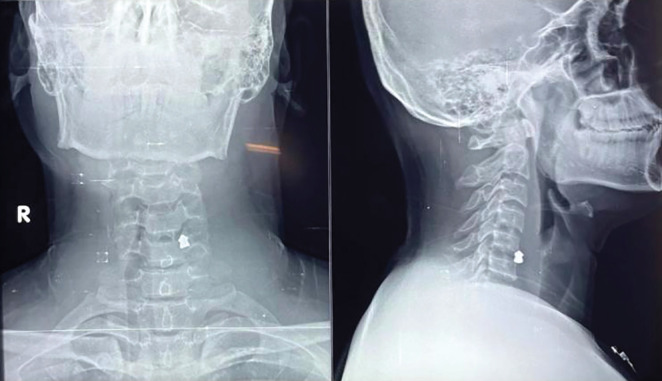

Airgun injuries are prevalent in the pediatric population. The present study described a case of air gun pellet injury to the left carotid artery and its successful management. A 25-year-old man presented to the emergency department complaining that his son had accidentally injured him with an air gun pellet while playing. The X-ray cervical spine revealed a single foreign body (pellet) located directly anterior to the C5-C6 vertebra. A CT angiography of the neck showed a spherical hyperdense object just anterior to the C6 vertebral body on the left side, 3 mm posteromedial to the left common carotid artery, which was most likely a pellet foreign body. The patient was sent to operation theatre (OT) for exploration. There was a rent in the internal carotid artery with active bleeding. After exerting both proximal and distal control, the rent was closed. Close air gun injury could result in gunshot wounds, as in the present case. Plain X-rays in AP and lateral view are required. Nonoperative management could be employed in a restricted group of patients with satisfactory outcomes. Those who have vascular involvement will require surgical intervention.